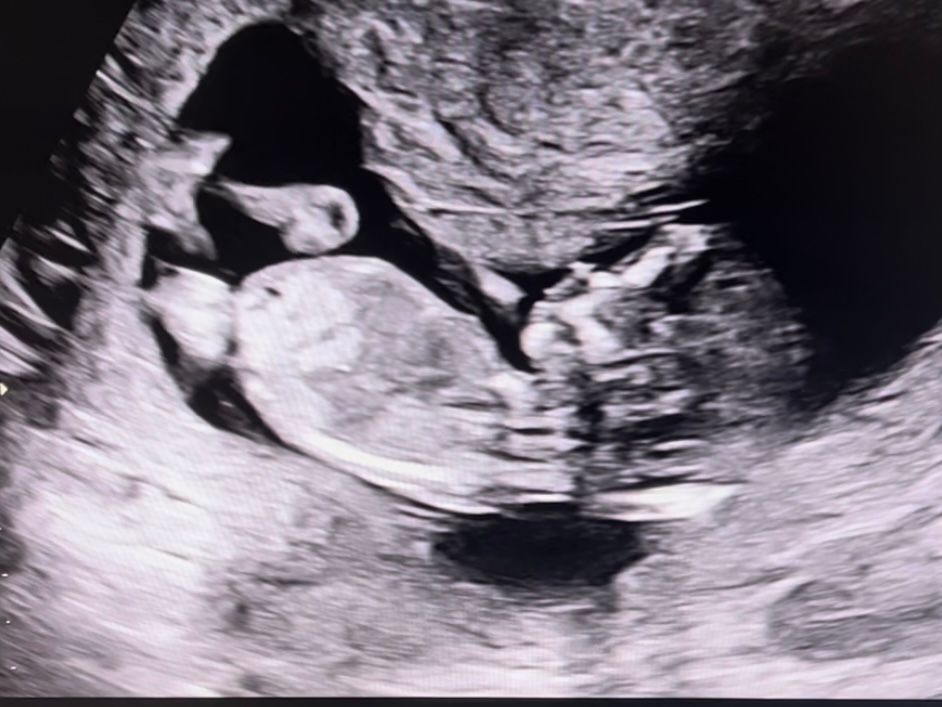

Девочки если я правильно понимаю это половой бугорок , на кого похож ребёнок, мальчик или девочка? Узистка даже предполагать не стала, говорит попозже приходить. И внешне и по половому бугорку. Хотя может это пуповина вообще 😅

У меня так же выглядел, но на самом кончике как бы бугорок был плавный переход такой, и врач сказал мальчик . Хотя по картинке из инета девочка, я видела такую же . Но врачу виднее🤭

Поздравляю с пройденным скринингом! Мне на 12 неделях предположила узистка мальчика, так и получилось. Подождите пару недель, там виднее будет. А на втором скрининге уже сами все увидите, если мальчик, то крупным планом))))